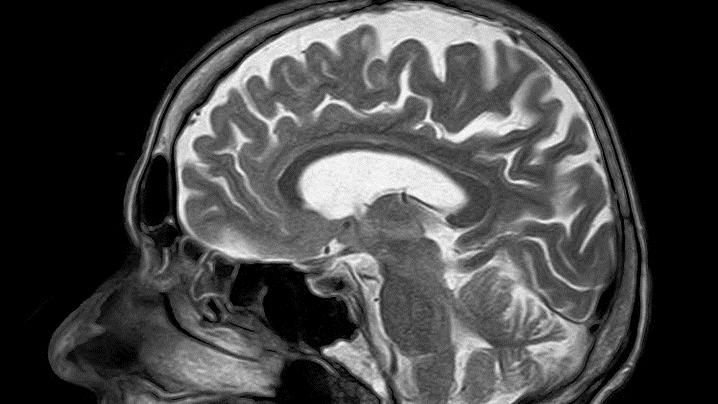

mri-782459_960_720

Pixabay | Pixabay

Znanstvenici su došli do revolucionarnog otkrića koje bi moglo pomoći u liječenju neuroloških bolesti, moždanih udara i raka. Radi se o implantatu ugrađenom u mozak koji bi pomogao u unosu lijekova u mozak.